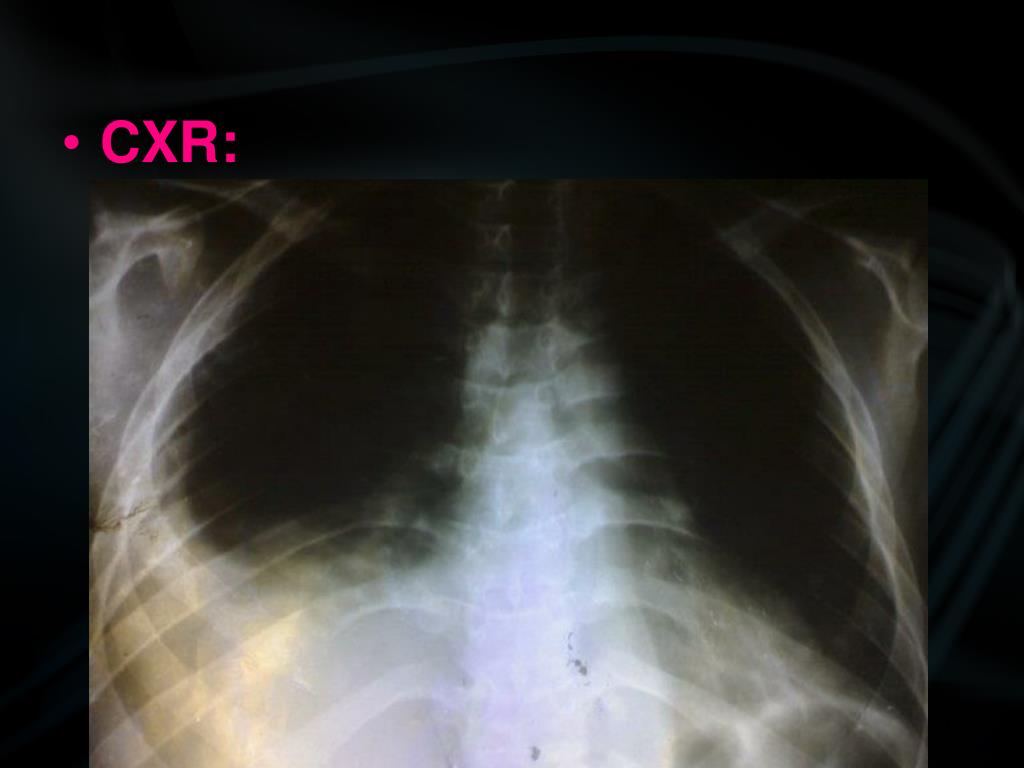

23. CXR: